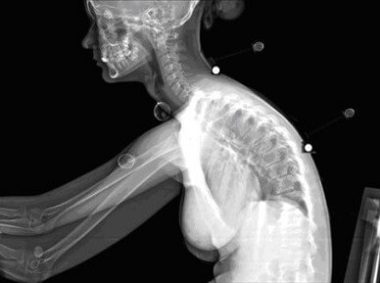

Poor posture is a really common cause of shoulder blade pain. There's that tell-tale pain between the shoulder blades and in the lower neck often accompanied by stiffness and discomfort.

In a world where we tend to spend lots of time hunched over at a desk, computer, sink or in the garden, poor posture and trapezius pain is a common problem.

The shoulders round forwards, the chin protrudes, chest and upper back muscles get weak. Areas of the spine stiffen, particularly the lower neck and upper back which can lead to aching shoulder blade pain, particularly across the upper back in between the shoulder blades.